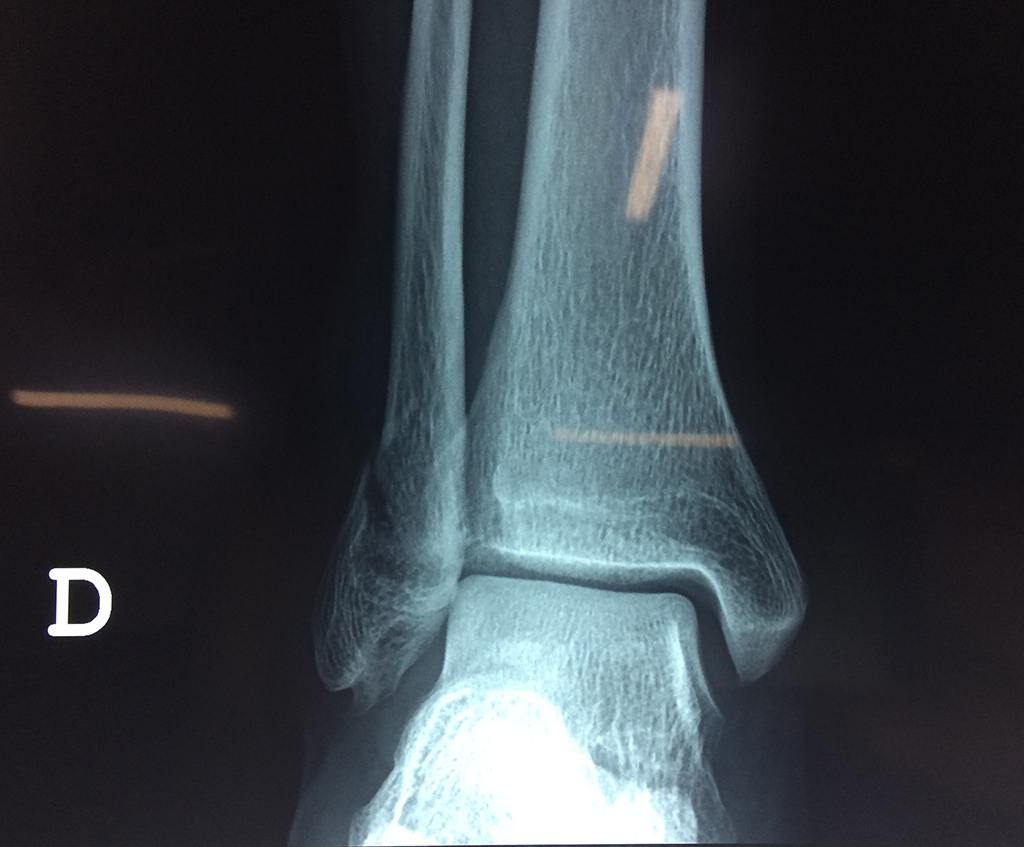

- Los extremos de los huesos están desalineados entre sí (desplazados).

- La fractura se extiende hasta la articulación del tobillo (fractura intra-articular).

Cuando se necesita cirugía, es probable que esta implique el uso de clavijas de metal, tornillos o placas para sostener los huesos en su lugar mientras la fractura se consolida. Los elementos de soporte pueden ser temporales o permanentes.